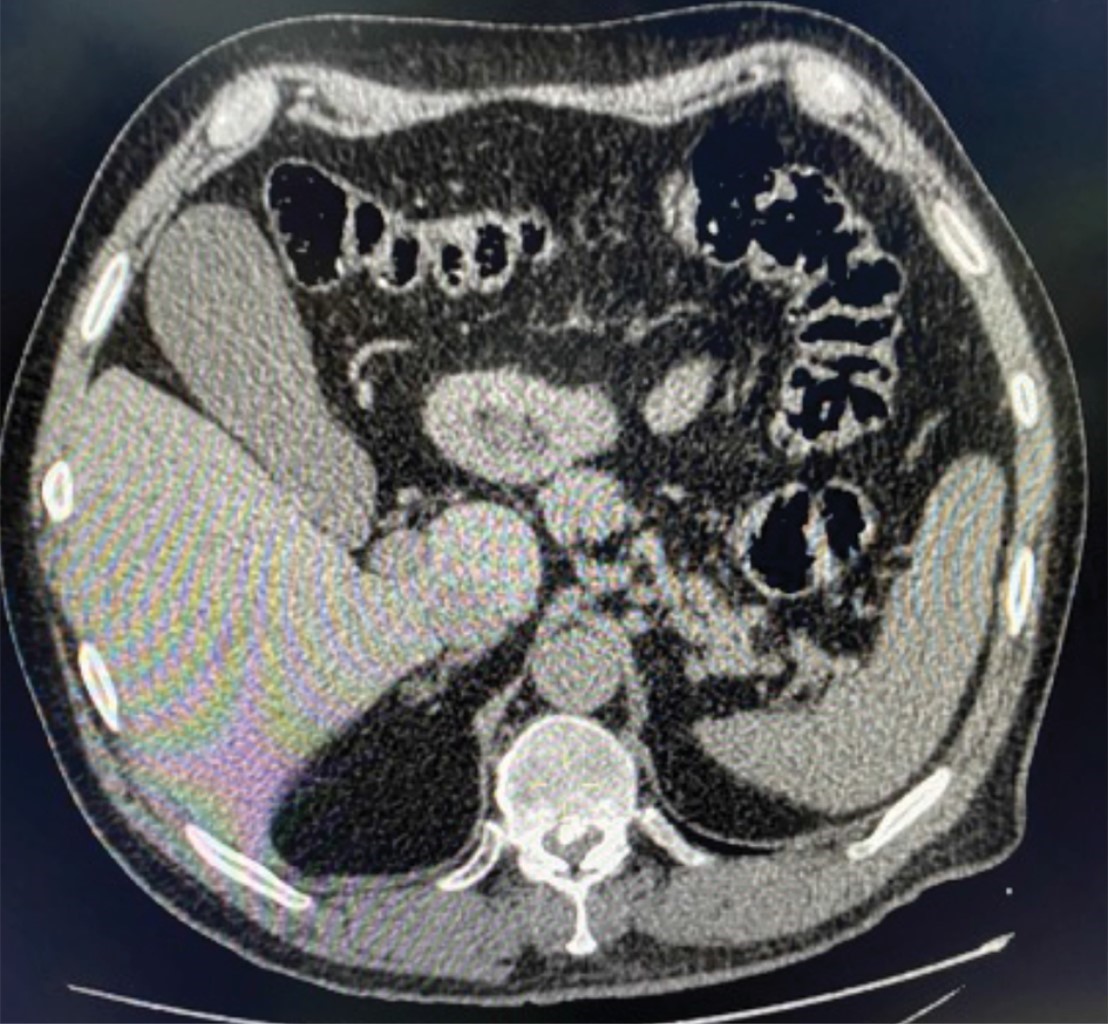

Ante la falta de diagnóstico preciso, se realizó tomografía de abdomen en donde no se pudo documentar alguna patología intraabdominal que justificara el dolor del paciente y que reportó nuevamente la presencia de lodo biliar, pero ninguna alteración vesicular o biliar agregada (Figura 2). Después de unas horas de observación sin analgésicos, el dolor volvió a incrementarse y fue más evidente su localización en el hipocondrio derecho. Un segundo ultrasonido, realizado por otro radiólogo, interpretó incremento generalizado de las dimensiones de la vesícula con franco engrosamiento parietal de 8 mm, escasa cantidad de líquido perivesicular, imagen en "tela de cebolla", signo de Murphy sonográfico positivo y ecos que ocupaban el cuello vesicular y proyectaban sombra acústica posterior (Figura 3). El paciente fue sometido a colecistectomía laparoscópica, donde se encontró vesícula severamente inflamada, con engrosamiento generalizado de su pared, gran distensión y datos de isquemia focal (Figura 4).

Figura 2